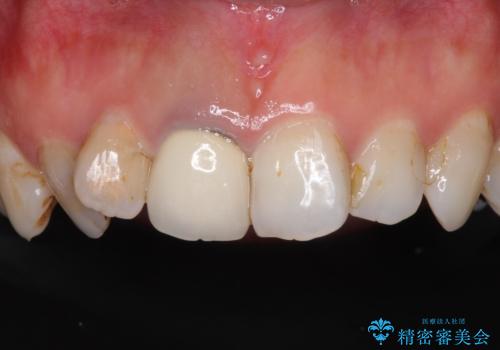

- 前歯の歯並びやむし歯治療の跡、奥歯の銀歯を気にして来院された患者様です。

インビザラインによる矯正治療の後に虫歯や銀歯をセラミックにて補綴することとしました。

前歯のむし歯治療の跡や奥歯の目立つ銀歯がなくなり、明るい口元になりました。